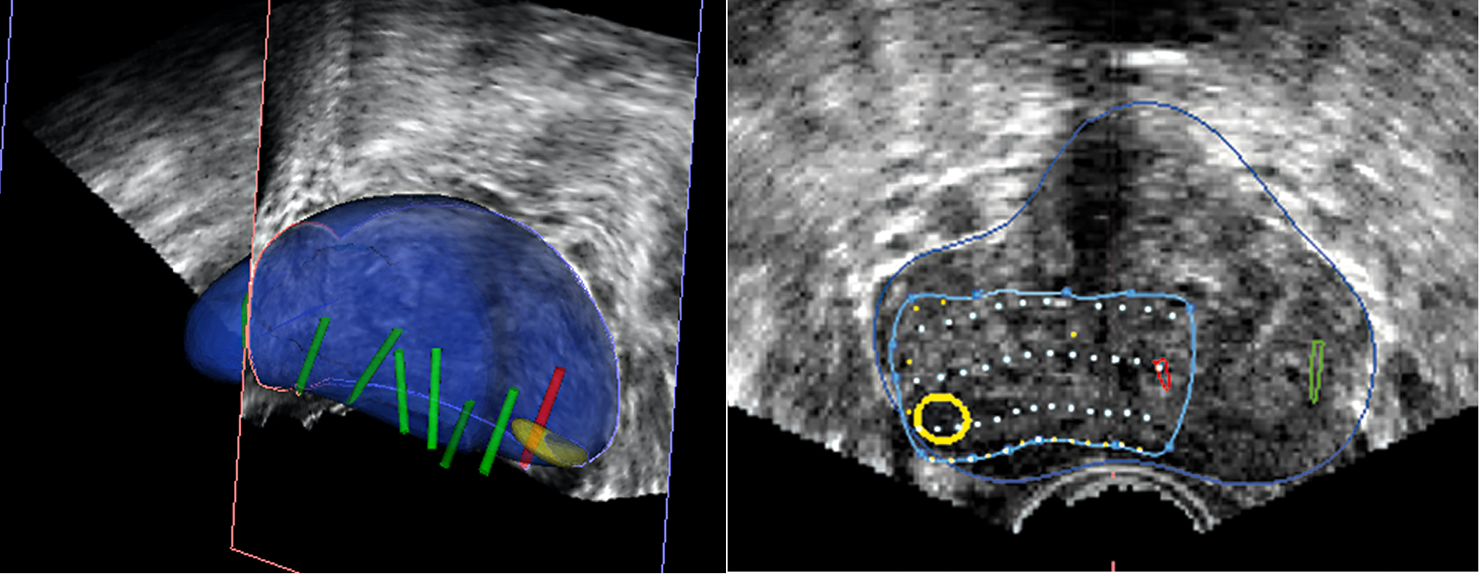

La próstata se escanea con la sonda de US. El operador define los contornos de la próstata y delinea las lesiones sospechosas a tratar en las imágenes de Resonancia. Los límites de la próstata se definen en la imagen en tiempo real de la próstata obtenida con la sonda trans-rectal del dispositivo. El software ejecuta automáticamente una «fusión elástica» de los dos volúmenes definidos, lo que conduce a una combinación tridimensional (3D) perfecta del volumen de RM con el volumen de la próstata en US. La misma fusión 3D se aplica al área sospechosa previamente identificada en la resonancia magnética y/o Biopsia por fusión que, por lo tanto, se puede identificar correctamente en la imagen en vivo de US. (Figura 7-8).

Fig. 7. Reconstrucción 3D biopsia por fusión, con cilindros negativos para cáncer(verdes), positivos (rojos) y área sospecha marcada en resonancia (amarillo).

Fig. 8. Planificación de tratamiento. Dibujo de la lesión a tratar, con margen de seguridad.

La terapia focal permite la preservación de la mayoría de tejido prostático normal, incluyendo los haces neurovasculares y mecanismos de la continencia urinaria. Adicionalmente, los avances en mpMRI y los mapas de Biopsias por fusión, definen precisamente la lesión objetivo y usando HIFU uno puede tratar solamente esa lesión o esa área a fin de mantener un margen de seguridad oncológica (Figura 8).